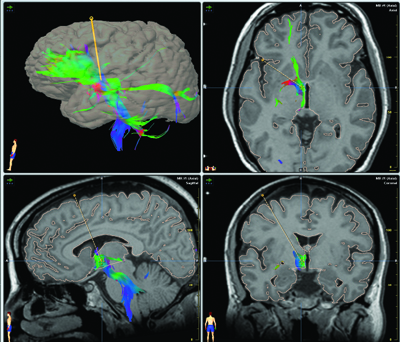

About the targets for deep brain stimulation in treatment resistant depression some options are available:

- The reward circuitry of the ventral striatum and Nucleus Accumbens has been associated with drug addiction and depression for many years. Some case reports showed some partial effect on TRD. One case report with obsessive-compulsive disorder and concomitant major

depression and three cases with TRD. - Subgenual Cingulate Cortex: Area 25. Helen Mayberg found the switch that lifts depression in area 25, a spot deep in the cortex. This area is the key conduit of neural traffic between the thinking frontal cortex or forebrain and the central limbic region that plays a role in emotions and which appeared earlier in our evolutionary development. This area is overactive during depression or sadness. This form of DBS was doen in a Randomized Controlled Trial with 6 patients with overall response of 60%.

- Inferior Thalamic Peduncle. The ITP has proven to be hyperactive in depression, a phenomenon that reverses with effective pharmacological treatment. Successful use of this target in DBS stimulation has been published in one case report. One initial case report indicates promise, large-scale trials of implantation are necessary to determine the efficacy and safety of this target.

- Rostral Cingulate Cortex: Area 24a. No electrode has yet been implanted in the rostral cingulate cortex in humans; however, stereotactic lesioning of this area has shown beneficial effects.

- Lateral Habenula. Only used in animal models with some suggestion that functional inhibition of this area using high-frequency DBS may have therapeutic benefit

These localizations have been described on this blog in another posts: 5 different locations for deep brain stimulation in depression, but now it appears in a peer reviewed article with excelent graphics.

Only three have been tried with patients with TRD or obsessive-compulsive disorder and concomitant major depression. The other anatomical targets are tentative. The most impressive results done with a proper study design was with Broadman area 25 by Helen Mayberg.